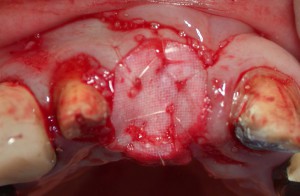

Y新聞社のGさん。前歯が1本歯根破折となり、抜歯しなければならなくなった。欠損となる部位の両隣りがすでに補綴されている歯(被せ物がしてある歯)であったのでブリッジも勧めてみたが、インプラントとなった。抜歯と同時にソケットプレザベーション(抜歯穴骨補填術)を行い、数ヵ月後に骨化を確認後インプラントを埋入した。もう少し口蓋側よりに位置どりをすれば、より審美的になったと考えられるが、当時の情報、知識、技量では精一杯だった。患者さん自身は満足されているが、術者本人は今から思えば改善の余地が多い症例である。

ソケットプレザベーションと前歯部インプラント(8年経過例)